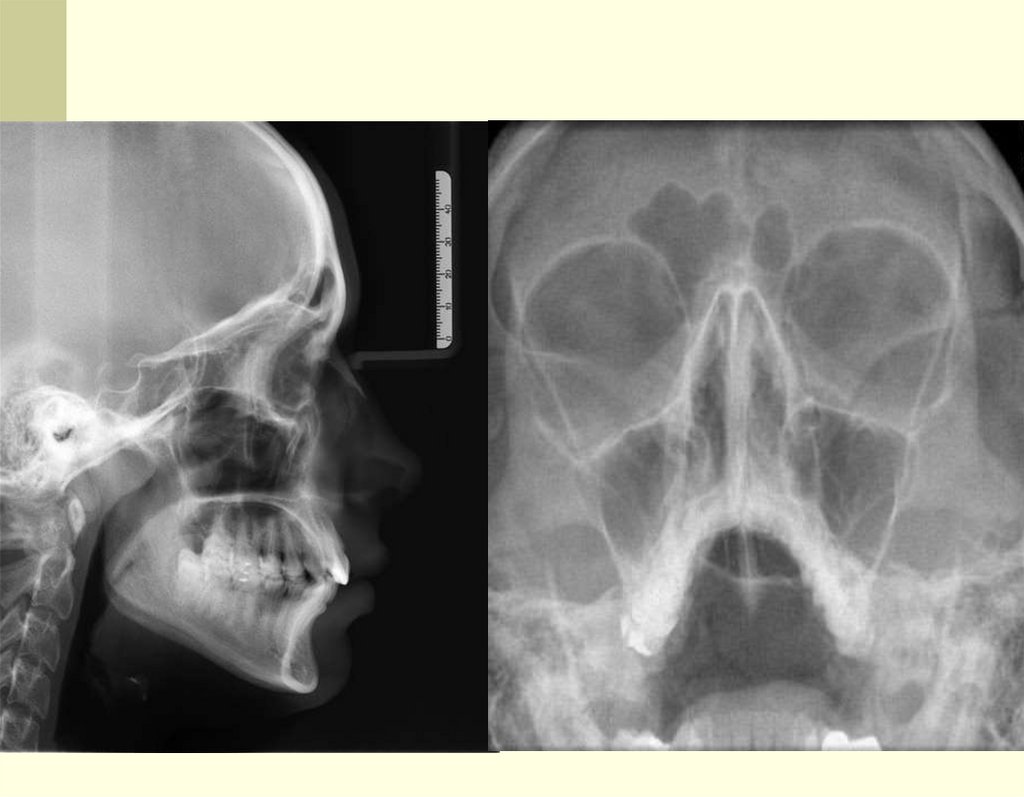

Медицинская краниология востребована запросами

неврологии, рентгенологии, МРТ и КТ.